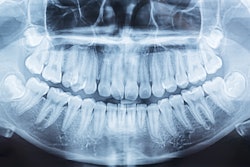

- Imaging reveals baby girl in SC born with 2nd mouth

Magnetic resonance imaging and computed tomography helped clinicians determine that a mass located on the chin of a newborn girl was a second oral cavity. The cavity contained unerupted teeth and an accessory tongue that moved in sync with her oral tongue, according to a case report. - Sugar substitutes lead to long-term changes in rats